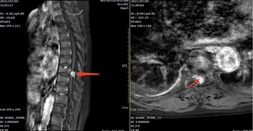

- 77岁的叶阿婆原本在家安享晚年生活,14个月前开始出现双下肢麻木乏力,症状逐渐加重,躯体麻木感平面逐渐上移,5个月前出现右下肢抬腿行走都很困难,需扶拐行走,近3个月甚至出现了二便乏力、排便困难。这让叶阿婆生活质量急剧下降,苦不堪言,当叶阿婆的儿女们得知漳州市中医院骨伤科是国家临床重点专科便驱车百余公里前来求诊。 骨伤科副主任王庆敏详细诊查后,考虑叶阿婆的症状为胸8/9椎管水平的脊膜瘤压迫脊髓神经引起。增强磁共振清楚显示椎管内...发布时间:2021-10-12